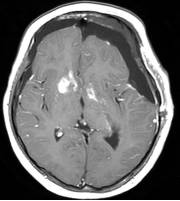

穿刺手术后患儿精神好,调养后3天行开颅手术切除肿瘤,经过14小时的艰苦奋战,顺利将肿瘤完全切除,手术后MRI见图5。患儿共住院23天,顺利康复、出院,出院时语言能力、四肢肌力均正常。

图5.手术后MRI显示肿瘤无残留迹象